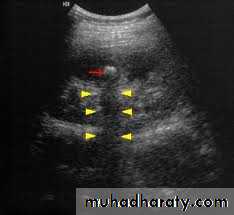

Ultrasound findings

1-Dilatation of the P.C.S. appears as multilocular fluid collection within central echo complex.-With more severe distention, dilated calyces appear as Multiple cysts but communicating with each other unlike true cysts.

2-Stones larger than 5 mm are easily seen on US but smaller ones may be missed.

-They produce intense echoes (hyperechoic) and cast acoustic shadows.

-Proximal and distal ureteric dilatation can be easily identified unlike mid-ureteric dilatation, and stones located in the middle third of the ureter are hard to be demonstrated unlike upper and lower ureteric stones (especially those lodged in the vesico-ureteric junction or pelvi -ureteric junction) which are easily identified by ultrasound.